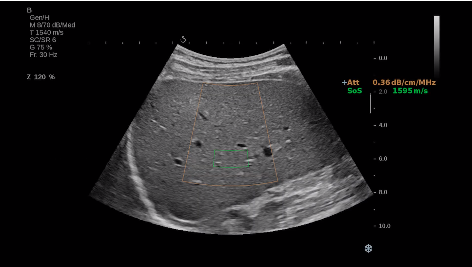

法國聲科影像(SuperSonic Imagine,SSI. Euroniex:FR0010526814)近日發(fā)表公告,宣布其研發(fā)的新一代“極速”超聲成像平臺(UltraFast Imaging),首次實(shí)現了肝臟的多項超聲定量評估新指標同步檢測,包括:Att PLUS,SSp PLUS和Vi PLUS等,基本涵蓋肝臟相關(guān)病理變化指征的如纖維化、脂肪變、炎癥等。據悉,此多項新技術(shù)新將搭載于新Aixplorer系列E超系統。

E超相關(guān)技術(shù)已被多項多中心大樣本研究證實(shí)對于肝纖維化無(wú)創(chuàng )評估有重要意義,同時(shí)也可全面應用于乳腺、甲狀腺、肝臟、前列腺、肌骨、婦科等全身各組織器官的定量評估和鑒別診斷。在慢性肝臟方面,聲科E超的肝臟相關(guān)定量診斷技術(shù)集,于2018年獲得美國FDA認證,成為FDA歷史上首次獲批的單病種超聲全面定量解決方案。